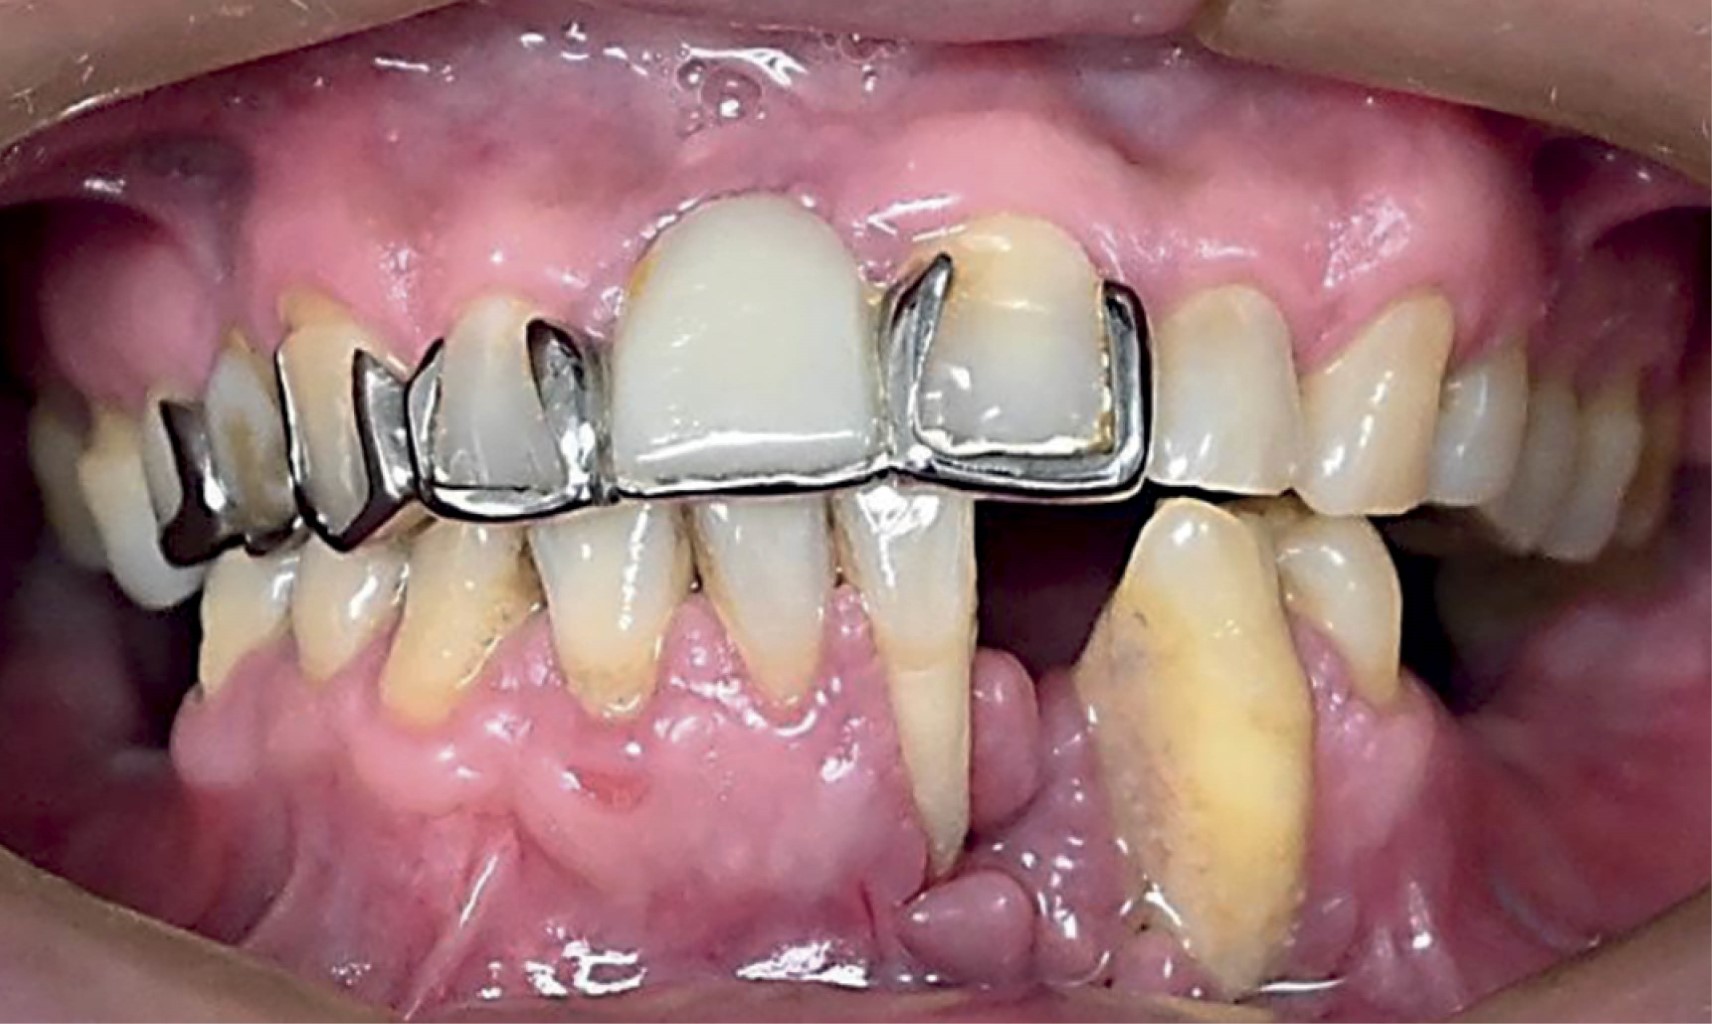

Presenta dolor 5/10 en escala visual analógica (EVA) en cuerpo mandibular izquierda, espontáneo, constante, sin exacerbación a la percusión horizontal y vertical de órgano dental canino izquierdo inferior. Niega presentar lesión en cuerpo, diaforesis o pérdida de peso repentina. Exploración extraoral sin evidencia de aumento de volumen, asimetrías o lesiones cutáneas-mucosas; intraoral, presenta defecto periodontal con recesión gingival asociado a órganos dentales incisivo central, lateral y canino inferiores izquierdos, con ulceración en región mencionada, movilidad grado III en órganos dentales mencionados (Figura 1). Sin presencia de adenomegalias cervicales a la palpación.

Figura 4